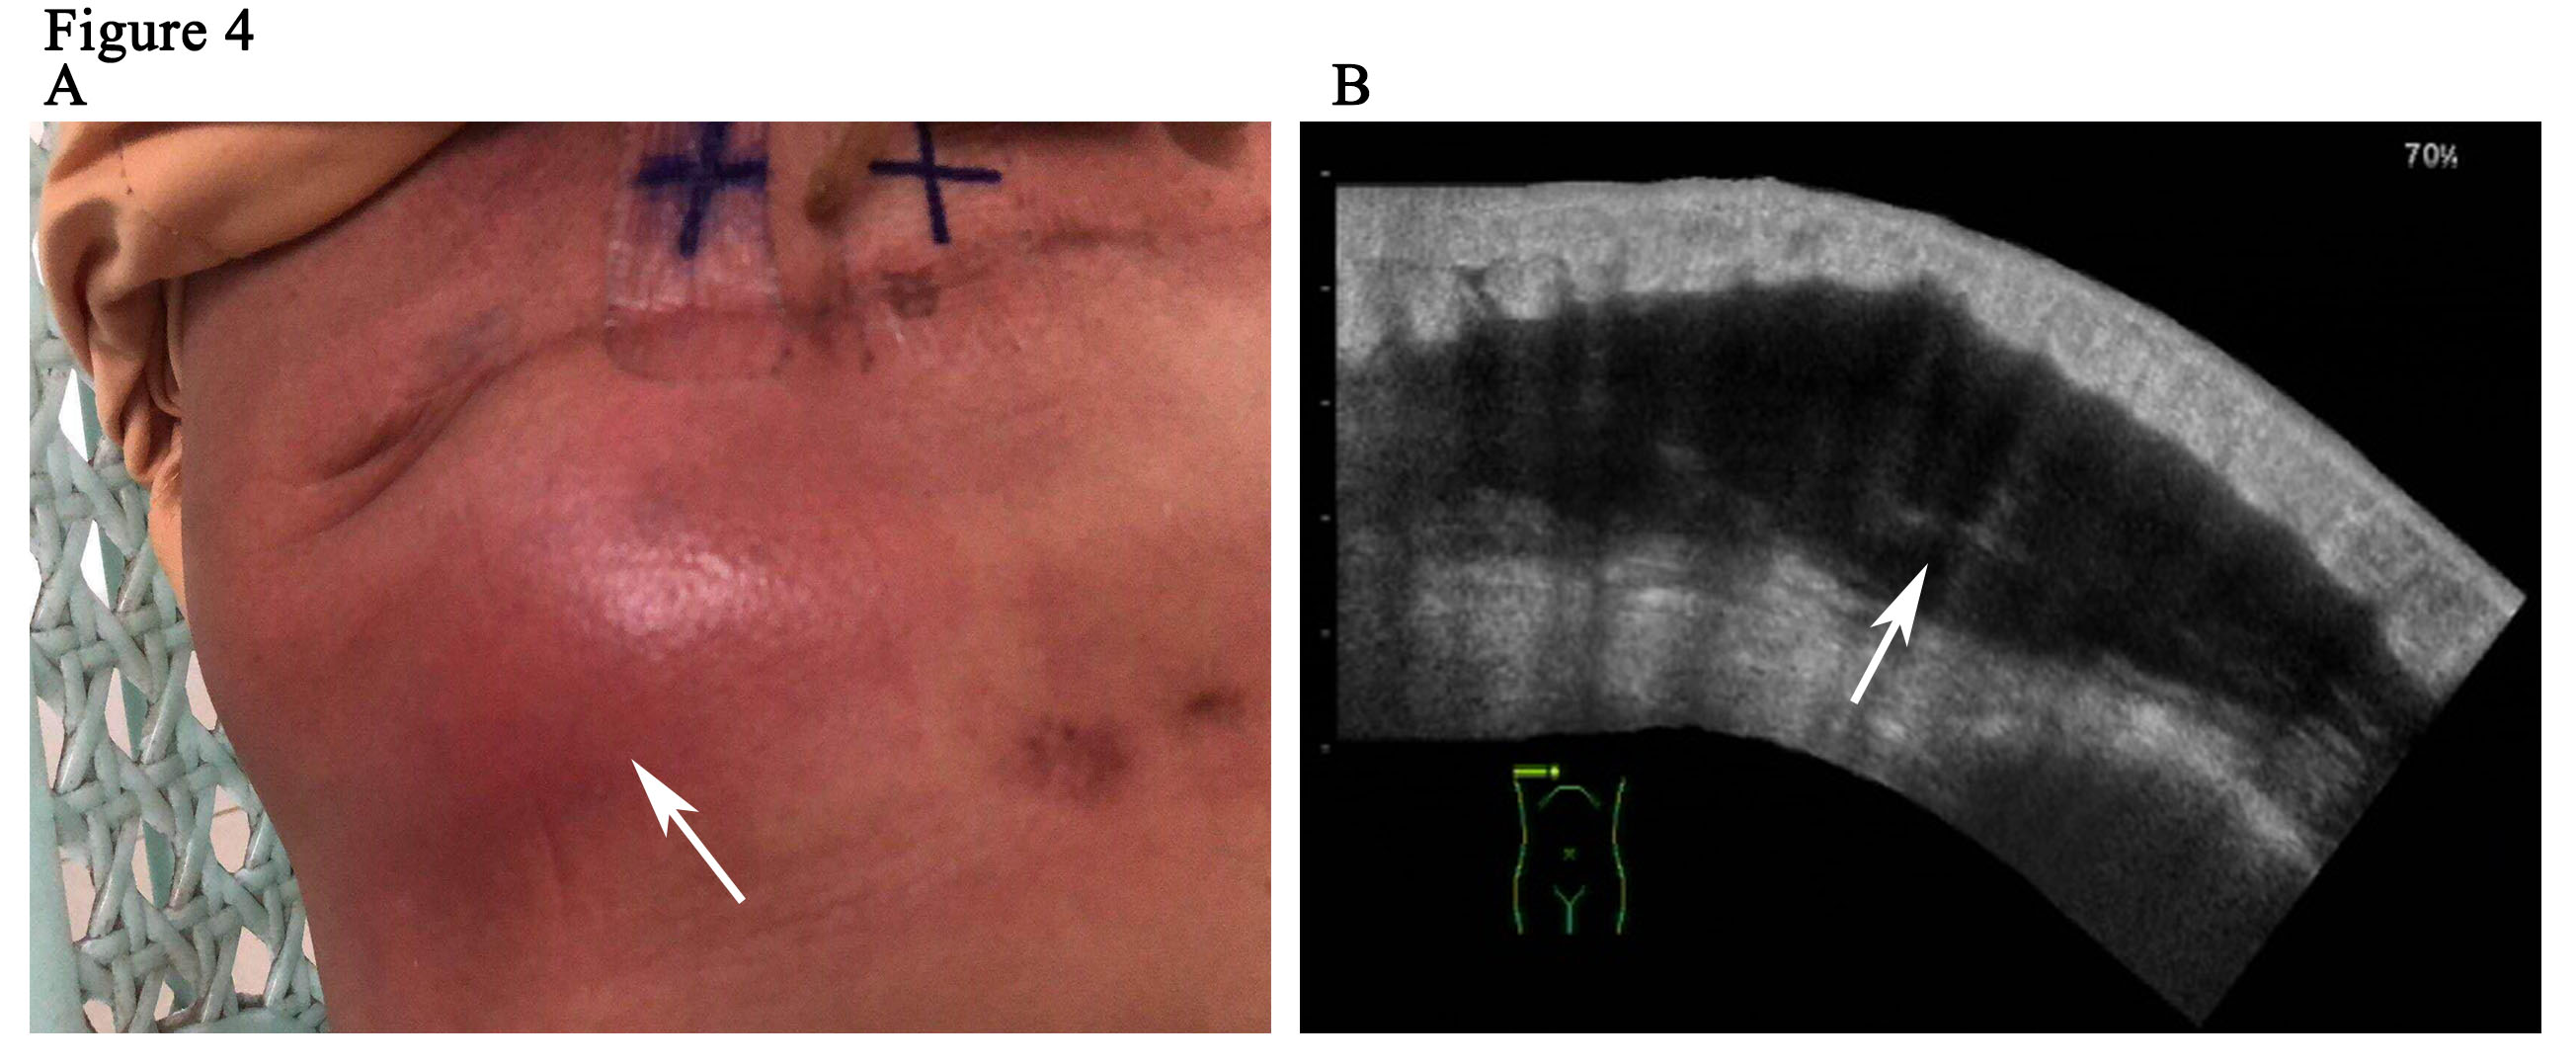

The patient is a 59-year woman. She had a mass for one month in the left upper outer quadrant region of the right breast. The patient had no past medical history or family history of breast cancer. Physical examination showed a mass of 3cm × 3cm sized, which was mildly tender and firm. The surface skin of mass was not ruptured. Lymph nodes of axillary and supraclavicular were not palpable. Ultrasound examination (Figure 1A) revealed a welldefined hypoechoic mass without calcification or evidence of invasion, which was 3.0cm × 2.6cm in size for the breast. The markers of erum tumor and other routine blood tests were normal. The bdominal and axillary lymph node ultrasound, chest X-ray and bone scan were normal. The patient was performed an excisional biopsy as an outpatient. Histopathology of a fast frozen section results showed an invasive ductal carcinoma. Following the diagnosis, she underwent a modified radical operation. The pathologist also confirmed there was an invasive ductal carcinoma (Figure 1B). 7 of the 22 dissected axillary lymph nodes demonstrated evidence of disease and the surgical margins were negative. The estrogen receptor (ER) was positive at 100%, progesterone receptor (PR) and human epidermal growth factor receptor-2 (Her-2) was negative. The tumor was pathologically staged as pT2N2M0 according with the eighth edition of the AJCC cancer [8]. An ultrasound of the patient’s breast was performed before she undertook the first cycle of chemotherapy. This ultrasound revealed a seroma of right chest wall measuring 7cm × 2.4cm in size (Figure 2). Then, the patient was performed adjuvant chemotherapy (AC) (doxorubicin + cyclophosphamide for 4 cycles, following by docetaxel cycled for 4 cycles). The patient then had another ultrasound of her breast after she had finished the last cycle of chemotherapy. The results of this ultrasound showed that the seroma of right chest wall now measured 10.8cm × 3.1 cm in size (Figure 3A). CT (computed tomography) scan also suggested a large seroma of the chest wall (Figure 3B). The seroma of the chest wall was enlarged compared with its size before starting chemotherpy. Once the round of chemotherapy was complete the patient then received adjuvant radiation therapy. The patient was treated with intensity modulate radiation therapy (IMRT). The planned dose was 50Gy (2.0 Gy/fraction x 25 fractions) to the affected areas (chest wall and regional lymph node). However, the patient had to stop radiotherapy when the accumulated dose was 38Gy, because she developed a soft tissue infection of chest wall. The right chest wall of secroma became red, swollen and painful. The region of infection was the same area where the seroma was (Figure 4A). Abscess had formed under the chest wall. Ultrasound revealed dense fine-dotted echoes in seroma (Figure 4B). The patient experienced a recurrent fever which resulted in her highest temperature being 39.8 ℃. A routine blood test revealed that leukocytes (14.9*10E9/L) and neutrophils (12.4*10E9/L) had increased significantly. C reactive protein (56.11mg/L) showed similar increases. The patient was then admitted to the Skin Repair Department. She was diagnosed with the right chest wall of secroma infection and abscess formation. The patient’s abscess was cut and discharged. Pathogen culture and drug sensitive test had was perform. Pseudomonas aeruginosa found in pus culture. Piperacillin sodium sulbactam, sodium cefmetazole sodium and ofloxacin were high sensitivity in drug sensitive test. She was then given antibiotics. The patient underwent three rounds of painful debridement and negative pressure treatment. Finally debridement and flap plasty was performed on the patient who then remained hospitalized for 2 weeks and after which went home for recuperation. Following discharge, the patient no longer had seroma and recovered well. She remains free of locoregional recurrence or distant metastases after 37 months of postoperative follow-up.

Figure 4: Soft tissue infection of chest wall (A). Ultrasound revealed dense fine-dotted echoes in seroma (B).